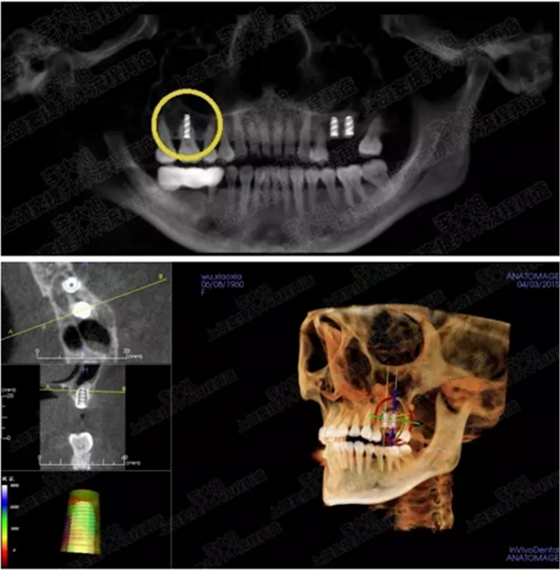

病例四

剩余骨量2mm-5mm且存在斜形竇底

007.png

提升8mm

008.png

009.png

病例五